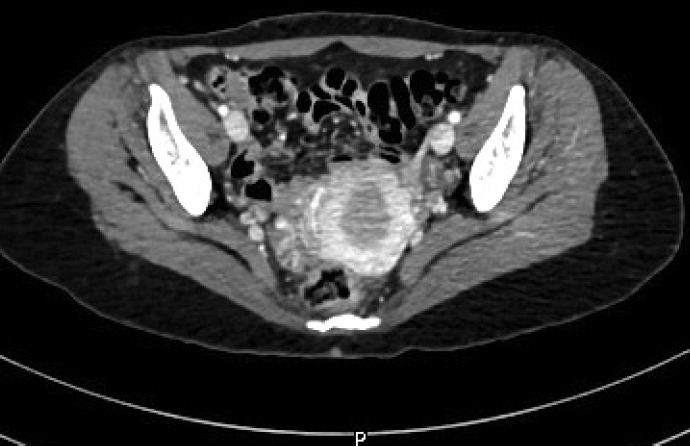

原发性骨细肌肉瘤非常罕见。从组织学上看,它与软组织的良性肌肉瘤相似。鉴于这种肿瘤的罕见性,只有在临床研究和检查排除了其他部位的转移后才能做出诊断。在此,我们又描述了一例原发性骨亮肌肉瘤。我们报告了一名 32 岁的女性患者,她因右膝关节疼痛就诊,影像学检查发现其右股骨远端肿块。活组织检查显示,肿瘤由纺锤形细胞束组成,呈不同形态排列,多形性明显。肿瘤细胞的平滑肌肌动蛋白呈阳性,desmin 和 H-caldesmon 阳性。影像学检查未发现体内有其他肿块。诊断结果为骨小梁肉瘤。鉴于原发性骨细肌肉瘤的诊断鉴别范围很广,因此了解这种罕见的骨肿瘤表型及其组织形态学和免疫组化特征对于准确诊断非常重要。

Primary leiomyosarcoma of the bone is rare. Histologically, it resembles leiomyosarcoma of soft tissue. Given the rarity of this entity, its diagnosis should be made only after clinical studies and workup have excluded metastasis from other sites. Herein, we describe an additional case of primary bone leiomyosarcoma. We report a 32-year-old female patient, who presented with right knee pain and was found to have a right distal femur mass by imaging studies. Biopsy showed a neoplasm composed of fascicles of spindle cells, arranged in different patterns, with significant pleomorphism. The tumor cells were positive for smooth muscle actin, focally positive for desmin and H-caldesmon. No other masses in the body were detected by imaging studies. The diagnosis of leiomyosarcoma of the bone was rendered. Given the broad diagnostic differential of primary bone leiomyosarcoma, it is important to be aware of this rare bone tumor phenotype and of its histomorphologic and immunohistochemical features for an accurate diagnosis.